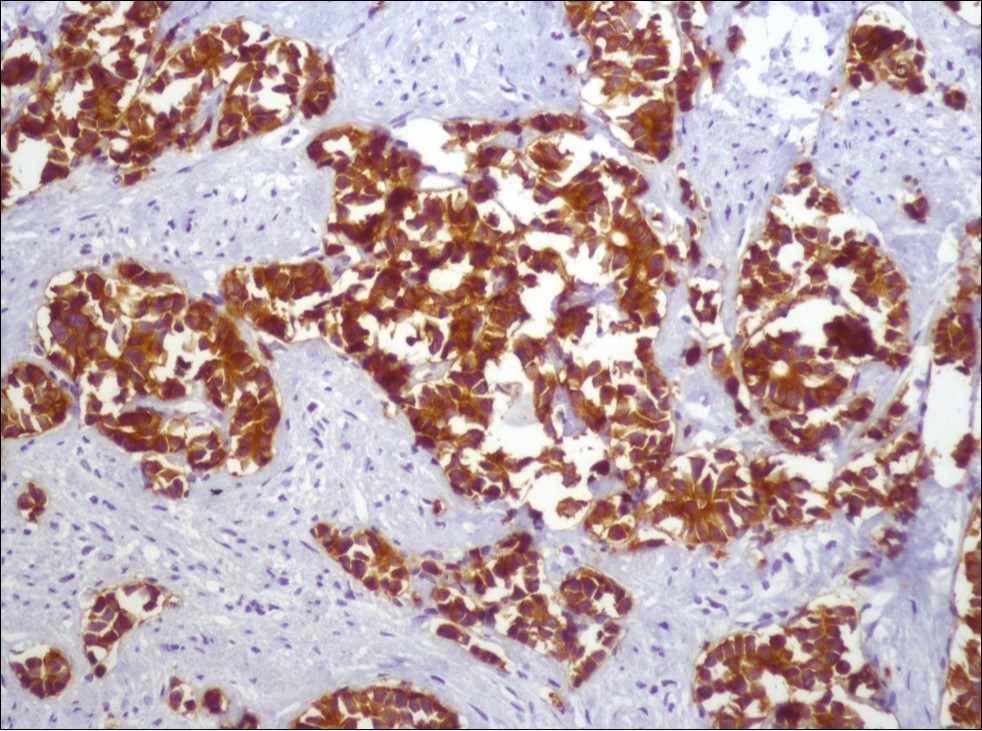

A 73-year-old male patient was admitted to our outpatient clinic with acute urinary retention. Digital rectal examination was normal. The PSA value was 1.81 ng/dl. Prostate size was 101 cc. Since the PSA value and digital rectal examination were normal, no biopsy was taken. Ultrasonography showed bilaterally ureterohydronephrosis. The creatinine level was 2.89 mg/dl. Hypertension has been presented as a comorbidity. An 18 Fr Foley catheter was inserted and alpha-blockers and 5-α reductase inhibitor medication was given. Creatinine level decreased to 0.91 mg/dl after one week. When the patient's catheter was pulled out, he could not urinate again. A catheter was inserted and waited one week more. After one week, the patient was unable to urinate again. The operation was decided due to this recurrent urinary retention. Because of prostate size was 101 cc and prostatic urethra was long, open prostatectomy was decided. When the prostate was removed during the operation, it was evaluated that the left side and the lower side were adhered to surrounding tissue. The prostate was removed as an en bloc. The catheter was removed after 5 days. The pathology of the patient has been reported as pure small cell prostate carcinoma. On the microscopic examination, the tumor was heavily infiltrated into the prostate parenchyma (Figure 1). Tumor cells were consist of atypical small-medium sized, mitotically active cells with a high nuclear to cytoplasmic ratio, hyperchromatic nucleus, nuclear molding, and inconspicuous nucleoli (Figure 2). On the immunohistochemically examination of synaptophysin showed diffusely and strong positivity while chromogranin A showed focal weak positivity with the absence of staining for PSA (Figure 3). Ki67 proliferative index was equal to 90% of the tumor cells (Figure 4). The results confirmed the diagnosis of prostatic small cell carcinoma. Metastatic lymph nodes were detected in the right perirectal region with metastatic multiple lymph nodes in the bilateral external iliac region, more on the left than in the PET CT. No metastasis was detected in the brain MRI and thorax computed tomography. Four cycles of etoposide and cisplatin chemotherapy were administered to the patient. Control PET CT taken after chemotherapy showed a significant decrease in size and metabolic activity of the right obturator and lymph nodes in the right perirectal area. The size and metabolic character of the left obturator, left external iliac and common iliac lymph nodes were increased. After a month, patient admitted to emergency outpatient clinic with left flank pain. There was an 8-cm mass in retroperitoneal area in the computed tomography. Supportive treatment was started because the patient could not tolerate chemotherapy. The masses reached to 13x11cm and fulfilled the retroperitoneal area. Multiple lung metastases were seen. The patient died 13 months later after the first diagnosis.